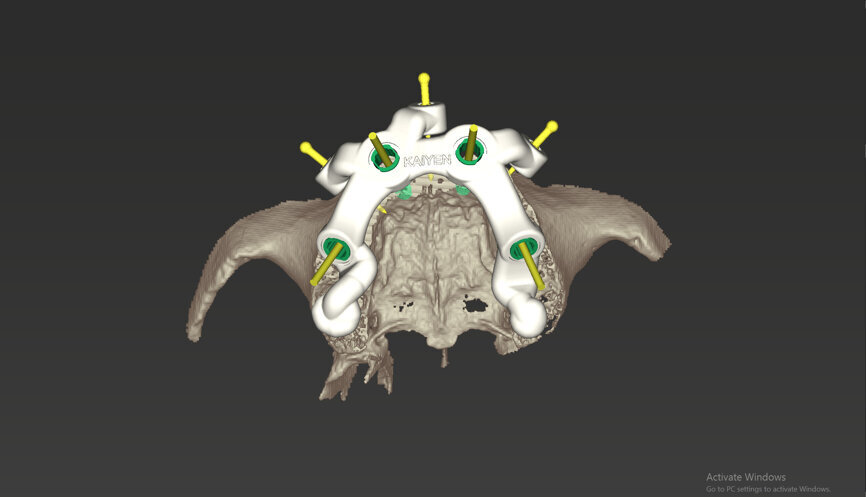

An intra-oral scan was taken to record the patient’s current oral situation, and the resulting STL file and the DSD fil (2D smile design image) were used to create the future prosthetic design with software for the laboratory (Figs. 3–6). The 3D radiographic DICOM data and the prosthetic design project STL file were superimposed in coDiagnostiX (Figs. 7–9) The fixation pin guide, bone reduction guide, surgical guide and bite registration guide were designed with coDiagnostiX (Figs. 10–13) and produced using 3D printing technology.

To design the prosthesis digitally, we first selected the screw-retained abutment (SRA) angle and gingival height (Fig. 14) and then we created the patient model on which we could connect the BLX implants with the SRAs selected from the Straumann library (Fig. 15). The implant placement guide was on the model, leveraging the high stability that we could gain from palatal support (Figs. 16 & 17). After printing the model, the BL  implant analogues were positioned using the template for navigation. The digital planning using coDiagnostiX (Version 9.14) allowed the dental technician to identify all the necessary parameters related to implant position (Figs. 18–22). Emergence profiles were set-up on the model (Fig. 23). The model was scanned using scan bodies, and a CAD/CAM temporary restoration was designed and milled in a PMMA-based restorative material (Figs. 24–29).